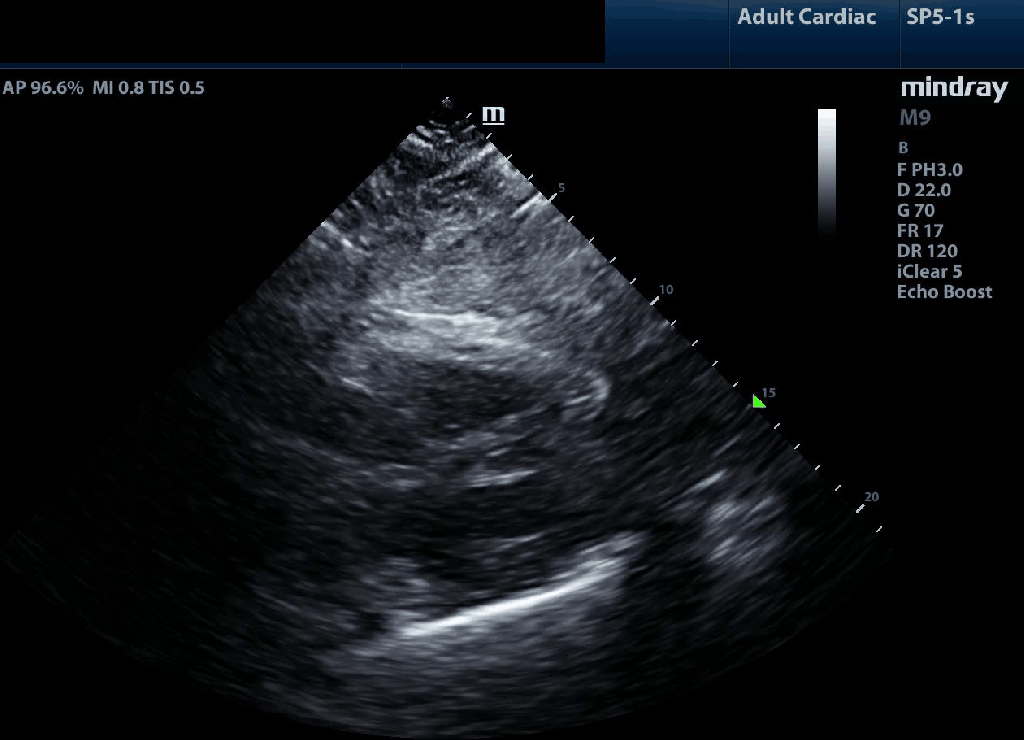

Practically, we support a qualitative approach where the question is geared toward identifying severe impairment; i.e. does the tricuspid annulus seem to move vigorously and around 2 cm by the depth markers toward the apex (image on the left below) or is there minimal longitudinal translation (as shown in the image on the right).

TAPSE can be estimated from the subcostal view using a similar approach but it is less common to see it used quantitatively as the alignment rarely allows for an accurate M-mode reading given the contraction moves across the screen as opposed to vertically. Normal visual TAPSE is shown on the left; impaired on the right.